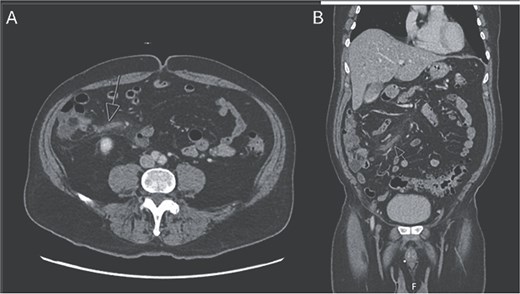

Upon arrival to the emergency department, the patient was hemodynamically stable and afebrile. On exam, the patient’s abdomen was soft, mildly distended, and tender in the right lower quadrant. He was noted to have a white blood cell count to 22.1, hemoglobin/hematocrit of 14.3/46.0, and platelets of 187. He had a lactic acidosis to 2.8. His electrolytes were unremarkable. CT scan of the abdomen and pelvis revealed no free air or free fluid, small amount of cecal wall thickening, and mild infiltrative changes within the mesenteric fat in the right lower quadrant with associated small mesenteric nodes with a normal-appearing appendix (Fig. 1).

CT abdomen and pelvis with IV contrast. A) Axial and B) coronal series identifying normal appendix and right lower quadrant mesenteric inflammatory changes.